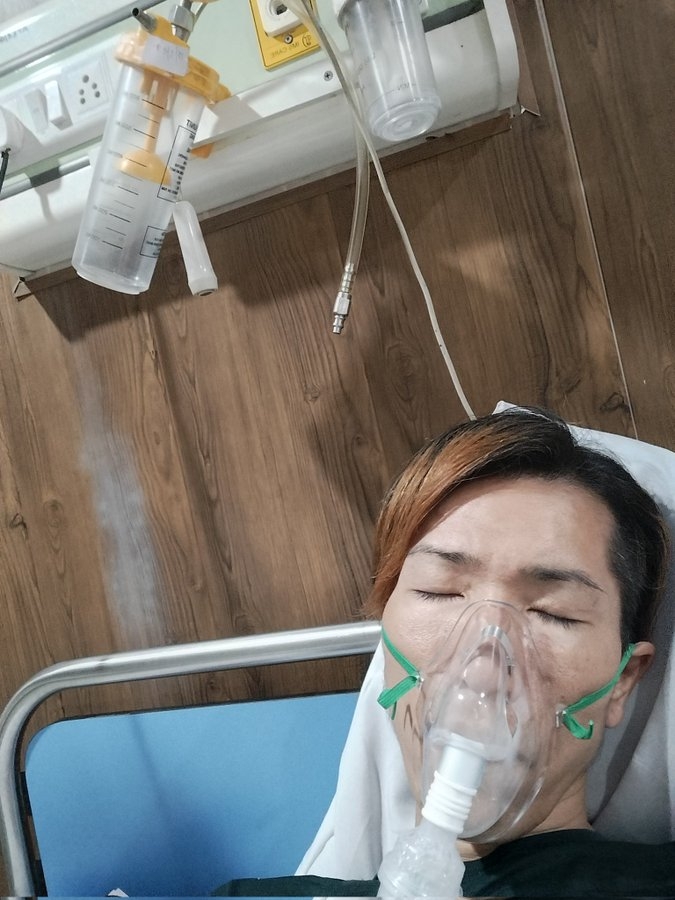

两人不久后出现剧烈发烧的情况,甚至严重到连站立和呼吸都感到痛苦,不得不紧急到瓦拉纳西当地医院求诊。住院4天期间身体极度虚弱,但院方准备的每一餐竟然都是咖哩,就连小食都是满满的香料,对于身体虚弱的他来说完全吃不下。

不仅如此,打点滴效果不好,他手臂肿得厉害。在蟑螂泛滥的病房住了4天,最终花费约152,980日圆(约7,470港元),没想到当初省下20卢比竟换来如此高昂的代价。